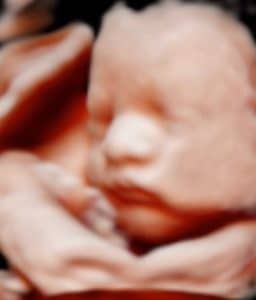

Pregnant Two Months After Tubal Reversal Surgery: Dream Came True!

Pregnant Two Months After My Surgery

pregnant-two-months-after-tubal-reversal-surgery-with-dr-monteithMy tubal reversal was May 7, 2019 and in only two months and I was pregnant.

Thank you Dr Monteith and staff for this blessing. Thank you so much for making my dreams come true.

Baby Landyn will be born one month before my one year tubal reversal anniversary.. Due 4-3-2020

Patient age: 39

Tubal ligation type: Tubal clips (clamps)

Patient hometown: Fellsmere, Florida